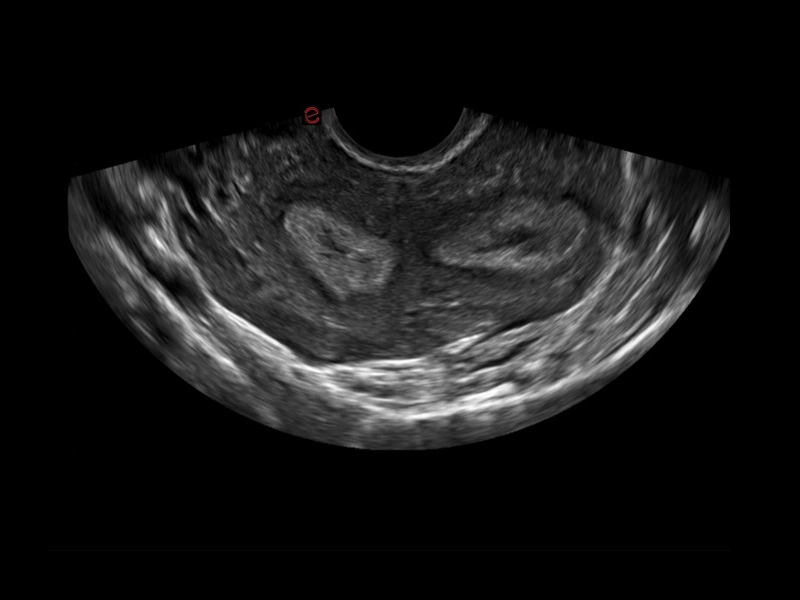

MyLab™C30 - Gyn 3D

MyLab™C30 - Gyn 3D